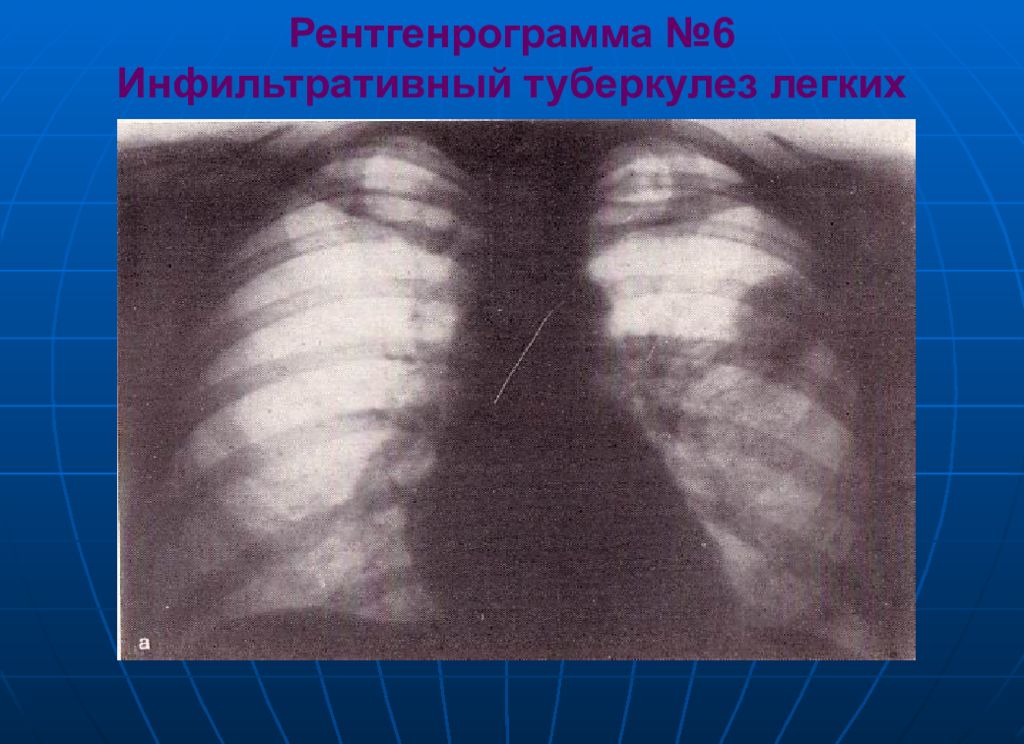

Иллюстрации по теме очагового и инфильтративного туберкулеза